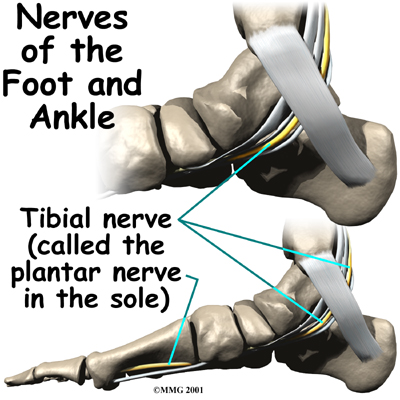

The nerve supply of the ankle is from nerves that pass by the ankle on their way into the foot. The

runs behind the medial malleolus. Another nerve crosses in front of the ankle on its way to top of the foot. There is also a nerve that passes along the outer edge of the ankle. The nerves on the of the ankle control the muscles in this area, and they give sensation to the top and outside edge of the foot.